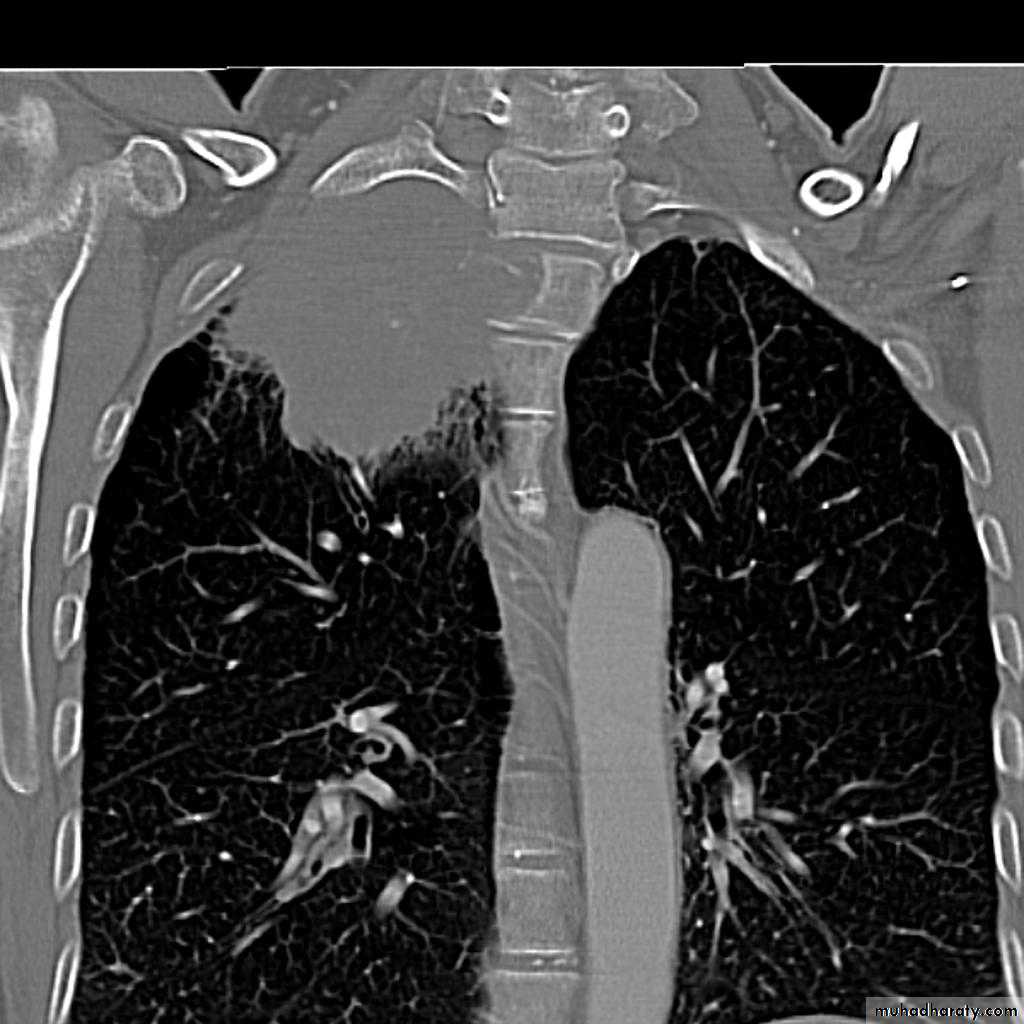

Right upper lobe collapse has distinctive features, and is usually easily identified on frontal chest radiographs .

Radiographic features

Chest radiograph

Collapse of the right upper lobe is usually relatively easy to identify on frontal radiographs. Features consist of :

increased density in the upper medial aspect of the right hemithorax

elevation of the horizontal fissure

loss of the normal right medial cardiomediastinal contour

elevation of the right hilum

hyperinflation of the right middle and lower lobe result in increased translucency of the mid and lower parts of the right lung

right juxtaphrenic peak

A common cause of lobar collapse is a hilar mass. When a right hilar mass is combined with collapse of the right upper lobe, the result is an S shape to elevated horizontal fissure. This is known as Golden S sign .